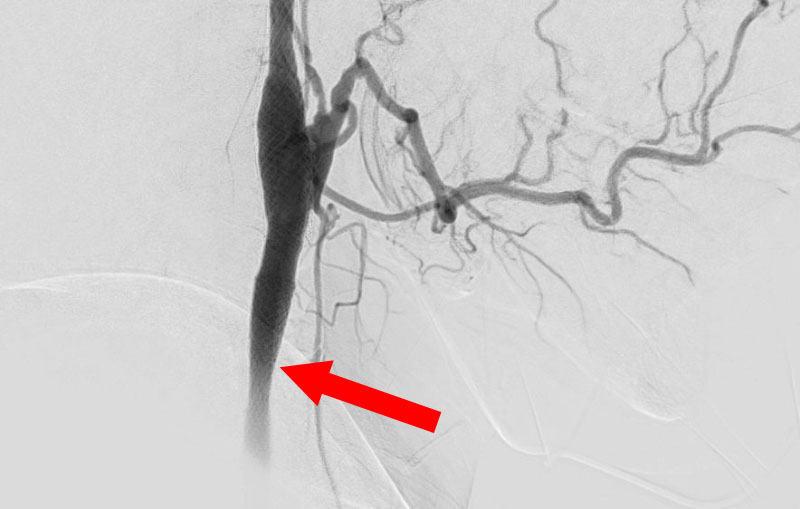

左頚部内頚動脈狭窄症

70代

院内外来

No.1499 手術前

No.1499 手術中

No.1499 手術後